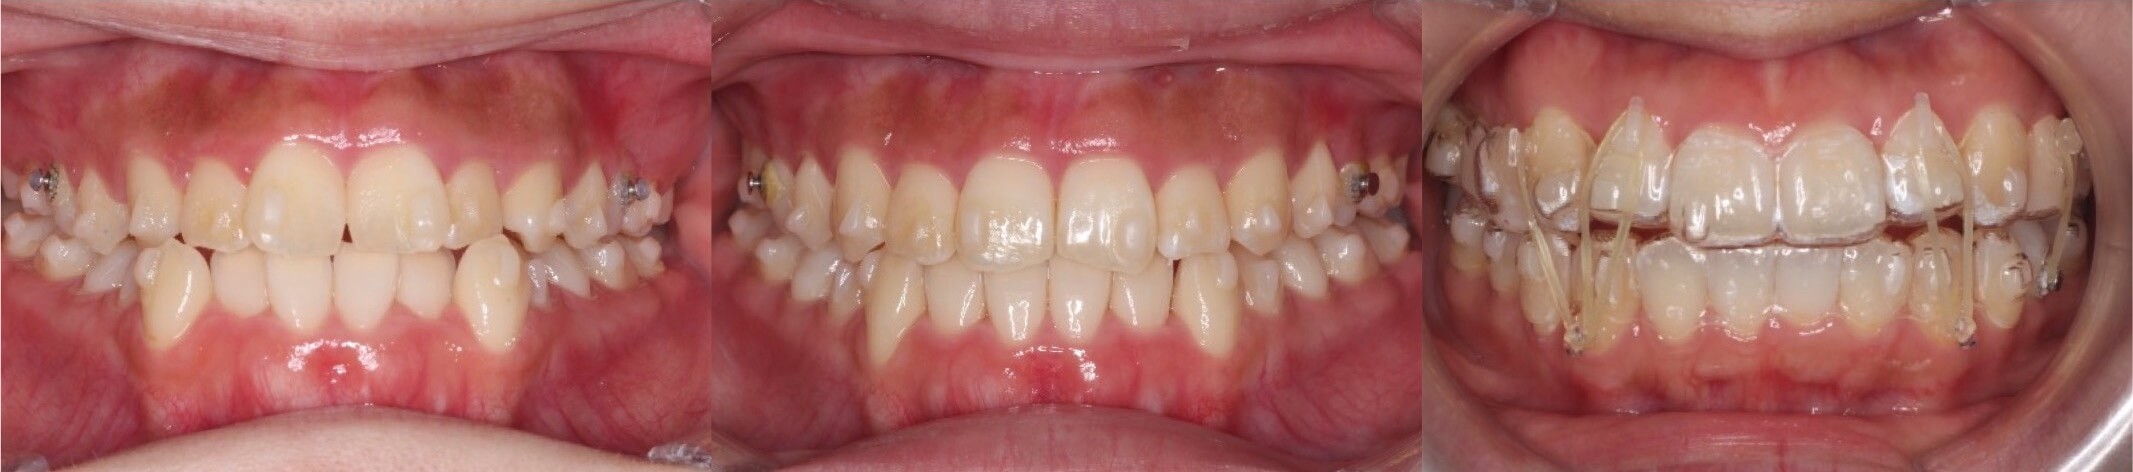

高校生女子・唇側矯正装置・アンカースクリュー

<症例概要>

主訴:八重歯

年齢・性別:15歳女性(高校生)

住まい:千葉県船橋市

症状:上下顎叢生・右側II級咬合

治療装置:唇側矯正装置

固定装置:歯科矯正アンカースクリューx1(右上頬側)

治療方針:右上奥歯の後方移動

抜歯:なし

治療期間:1年9か月

リテーナー:上プレートタイプ+下フィックスタイプ

治療費用:968,000(税込)

代表的副作用:痛み・治療後の後戻り・歯根吸収・歯髄壊死・歯肉退縮

▶︎その他の副作用

右側が八重歯になっているケースです。右上の奥歯をアンカースクリューを使用して後ろに後方移動してできたスペースに犬歯を配列しました。写真ではスクリューの使い方はわかりずらいのですが、玄人好みの治療です。歯科矯正アンカースクリューを使用する事で通常では難しい歯の動きをも能にしてくれます。

アンカースクリューは歯槽骨が安定する15歳以上の患者さんに使用しています。将来的には埋まっている親知らずは再発防止のため抜歯を推奨しています。